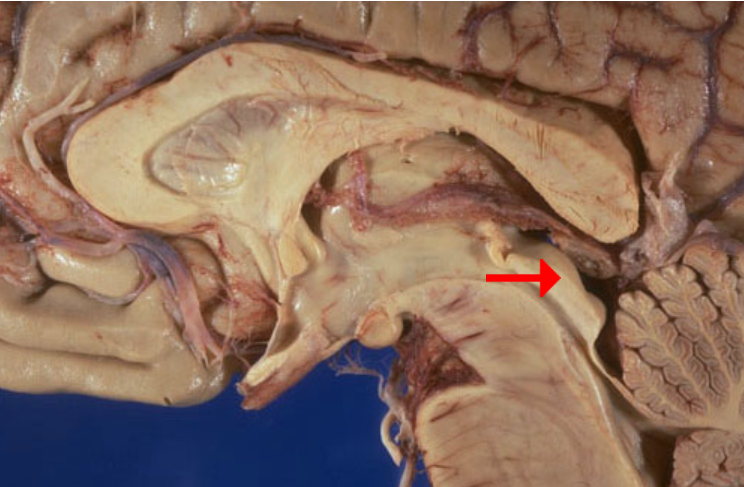

Label this brain part

Aqueduct of Sylvius

Label this brain part

Tectum (of midbrain)

Label this brain part

Fornix

Label this brain structure

Caudate nucleus

Label this brain structure

Putamen

Label this brain structure

Globus pallidus

Label this brain structure

Amygdala

Label this brain structure

Septum pellucidum

Label this brain structure

Optic chiasm

Label this brain structure

Cingulate gyrus

Label this brain structure

Substantia nigra

Label this brain structure

Optic tract

Name this brain structure

Hippocampus

Label this brain structure

Cerebral aqueduct

Label this brain structure

Superior colliculi

Name this brain structure

Fornix

Label this brain structure

Pineal gland